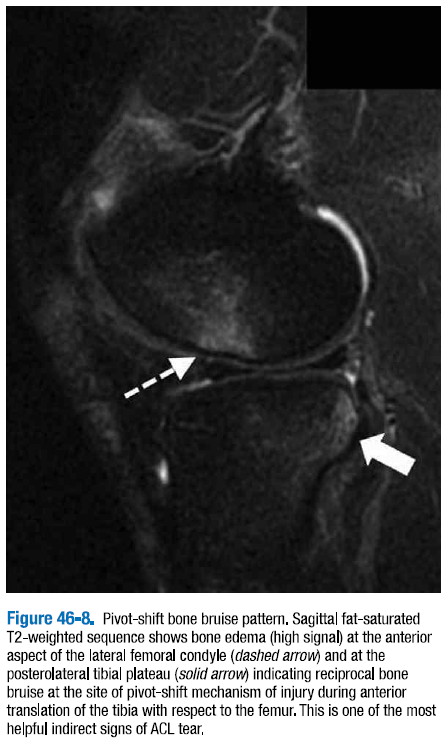

△ 그림 46-8. 추축 이동 골 타박상 패턴

시상면 지방 포화 T2 강조 시퀀스는 외측대퇴골과(점선 화살표)와 후외측 경골 고평부(굵은 화살표)의 전방에서 골부종(높은 신호)을 보이는데, 대퇴골에 대하여 경골의 전방이동이 일어나는 동안 추축 이동 메커니즘의 부위에서의 상호적 골타박상을 암시하는 것이다. 이는 전방십자인대 파열의 가장 간접적인 징후 중 하나이다.